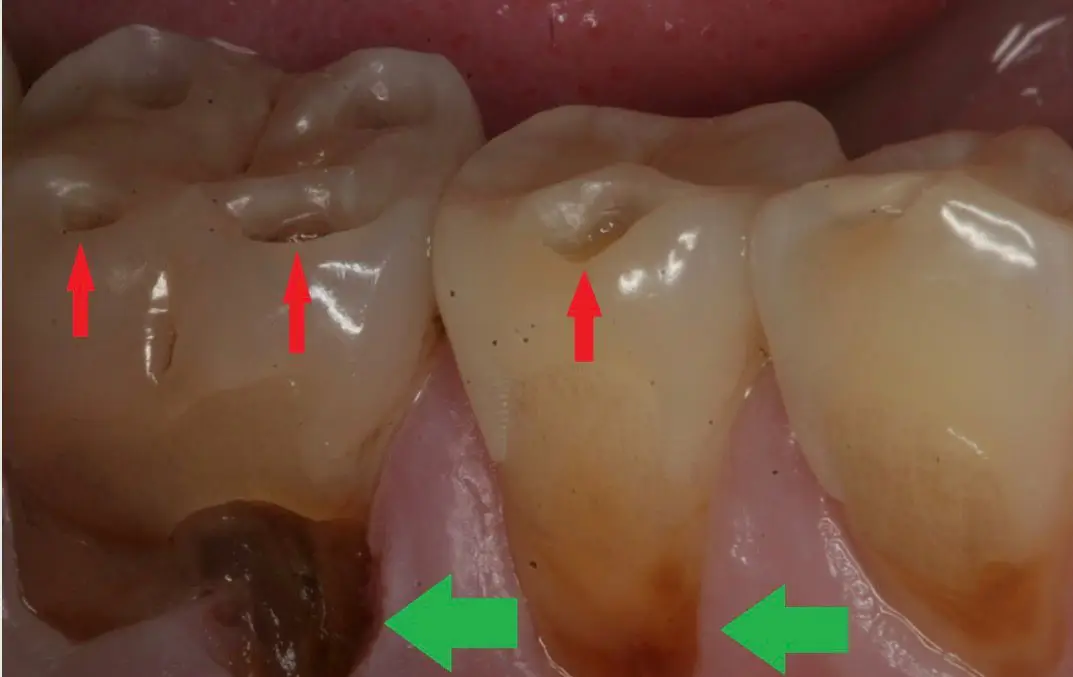

Do You Really Need a Crown After a Root Canal? What Modern Dentistry Actually Says Quick answer: Not always. For

Fibre-Reinforced Biomimetic Dentistry: Why Ribbond and EverX Are Quietly Changing How We Save Teeth Some of the most important shifts